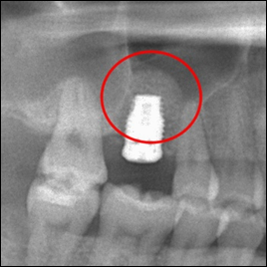

インプラント埋入後のレントゲン写真